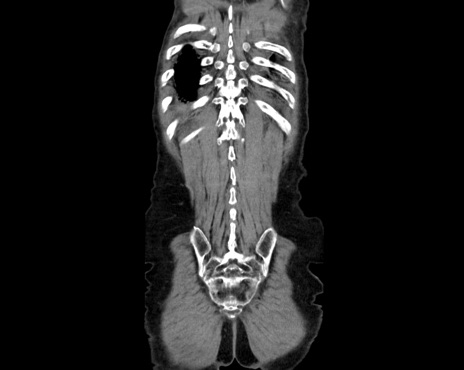

横断像

【症例】80歳代男性

【主訴】嘔吐

【現病歴】昨晩2回嘔吐あり、今朝になっても嘔吐あり。来院。

【既往歴】胃潰瘍

【身体所見】意識清明、BT 37.6℃、BP 166/95mmHg、HR 100bpm、SpO2 97%、腹部:平坦・軟、腸蠕動音聴取良好、圧痛なし。

【データ】WBC 21900、CRP 1.4